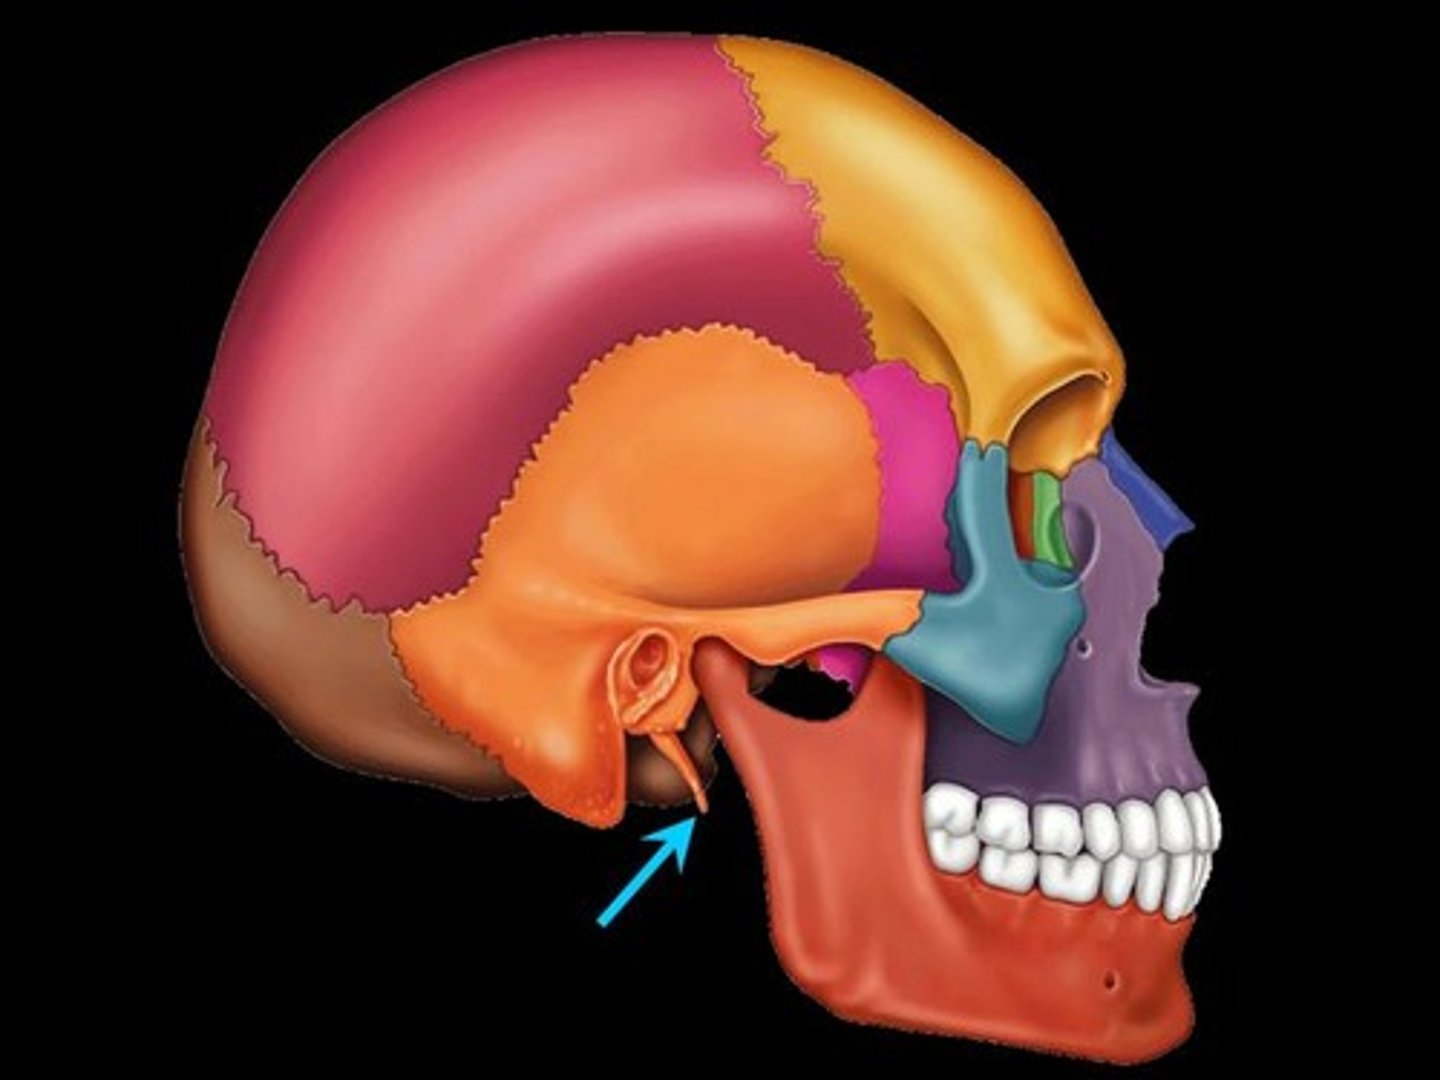

temporal bone

zygomatic process

mastoid process

styloid process of temporal

What is B

frontal bone

What is A

ethmoid

What is C

sphenoid

what is D

Palatine

What is E

Zygoma

What is F

Maxilla